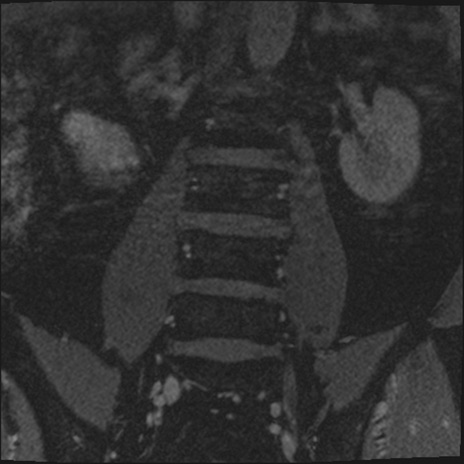

【整形】TIPS症例2 腰椎MRI 3D(冠状断像)

【症例】70歳代男性

【主訴】左下肢痛

【現病歴】2週間前くらいから腰痛、左下肢痛あり。左臀部から大腿、下腿外側のしびれが常時ある。歩行とともに同部位の痛みあり。

【身体所見】Lasegue70-/60+、Bragard-/±、PTR ±/±、ATR -/-、IP 5/5、TA 5/4、TS 5/5、EHL 右第1足趾なし/3、FHL 5/5、hypersthesia(-)、足背動脈触知良好

異常所見と診断は?